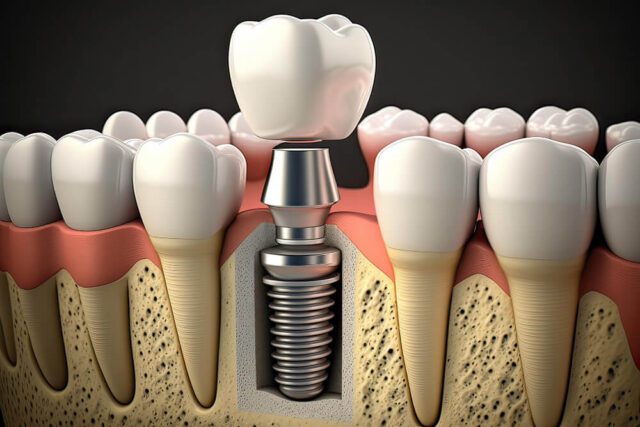

زراعة الأسنان والتركيبات عالية الجودة

تعتبر زراعة الأسنان هي الحل الأمثل لتعويض الأسنان المفقودة بشكل دائم. نقدم في مدونتنا إرشادات حول المراحل المختلفة لـ زراعة الأسنان، وتقنيات الزراعة الفورية، ومعلومات عن أنواع الزرعات المستخدمة (والتي نستخدم منها الأفضل عالمياً). كما نوضح كيفية العناية بـ التركيبات الثابتة والمتحركة لضمان استمراريتها لمدى الحياة.